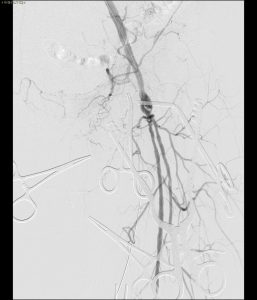

Il paziente si è presentato alla nostra osservazione con una storia clinica di EVAR (effettuata circa un anno prima con endoprotesi aortica Cook). Gli esami di controllo mediante angio-TC hanno rivelato una complicanza severa: la trombosi completa dell’innesto al di sotto delle arterie renali.

Di fronte a questo scenario, l’équipe ha optato per una strategia “endovascular-first”, con l’obiettivo di ricanalizzare i vasi riducendo al minimo l’invasività per il paziente.

- Analisi del caso: Trombosi completa endograft

- Ricanalizzazione con filo guida

- Predilatazione

- Stenting